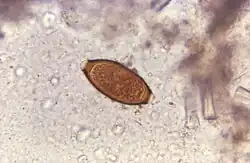

Terapia con huevos embrionados de Trichuris suis

La enfermedad de Crohn es poco común en las partes del mundo donde la población está expuesta a gusanos parasitarios (helmintos). Algunos investigadores piensan que los estilos de vida modernos, altamente higiénicos, podrían contribuir al riesgo de desarrollo de la enfermedad de Crohn.[124] La idea subyacente a este enfoque se ha denominado la hipótesis de la higiene. Por otro lado, los helmintos disminuyen la respuesta inmunitaria en humanos colonizados naturalmente y reducen la inflamación en la colitis experimental.[124] Bajo este contexto, se especuló que la infección con helmintos podría ser favorable para la enfermedad de Crohn.[125] Se realizaron ensayos utilizando huevos embrionados del parásito Trichuris suis (tricocéfalo que afecta a los porcinos) que mostraron resultados prometedores en personas con enfermedades inflamatorias intestinales.[126][127][128] En uno de los ensayos con resultados más optimistas, el 79,3 % de los pacientes mostró respuesta al tratamiento, y el 72,4 % entró en remisión.[124] Ensayos posteriores han encontrado resultados menos alentadores. Los ensayos TRUST-I y TRUST-II fracasaron en fase 2 y se interrumpieron.[129][130] Un ensayo en 2017 no encontró ninguna dosis que mostrase un efecto clínicamente relevante sobre el placebo.[131] Un metaanálisis en 2018 concluye que «el tratamiento con TSO estadísticamente no mostró ningún beneficio para los pacientes con enfermedad inflamatoria intestinal, por lo que sugiere a los médicos que consideren cuidadosamente su valor antes de ponerlo en práctica clínicamente. Tal vez sean necesarias investigaciones continuas con muestras de mayor tamaño debido a que los resultados anteriores carecen de fuerza».